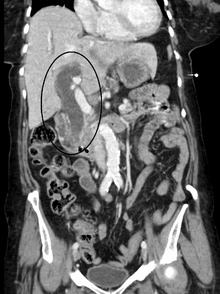

Biliary tract dilation due to obstruction as seen on CAT scan

Biliary tract dilation due to obstruction